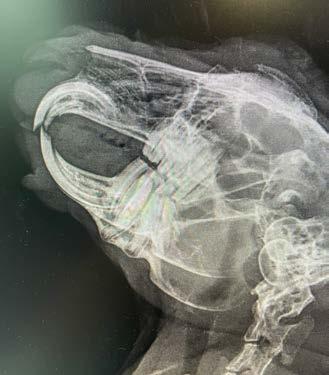

Figure 1. Lateral radiograph showing diffuse idiopathic skeletal hyperostosis (DISH)

Figure 2. Dorsoventral forelimb and cervical spine Figure 3. Lateral thoracic spine Figure 4. Ventrodorsal hips

Figure 5. Ventrodorsal cervical, thoracic and lumbar spine

Opal has diffuse idiopathic skeletal hyperostosis (DISH). This can cause limited spinal range of motion, nerve impingement leading to spinal pain and pain on the legs. The nerve impingement can also cause muscle weakness, paresis, and changes in spinal reflexes.

Opal was diagnosed with diffuse idiopathic skeletal hyperostosis (DISH) after discussion with Dr Richard Malik, as I had never actually seen a case like this before.

DISH is a systemic non-inflammatory disorder of the axial and peripheral skeleton that has also been described in humans and dogs.

DISH results in the ossification of soft tissues including spinal ventral longitudinal ligaments and sites of attachment of tendons and capsules to bone. In dogs and humans the prevalence increases with age.

Clearly—the skeletal changes in this cat ARE SEVERE. There is every possibility that there is intervertebral disc protrusion adding to the cat’s disability by compressing the spinal cord or nerve roots exiting intervertebral foramina. The only way to determine this is by advanced imaging, CT, a CT myelogram, or an MRI scan (ideally all three!). The problem of course is we do not know what causes DISH in cats or dogs, and we cannot treat the underlying problem, so even if there is a discrete surgical lesion—can we be sure fixing it will help the cat? And the imaging would likely cost $5,000 and surgery might cost another 5-10 thousand dollars. A lot of money to pay with an uncertain prognosis.